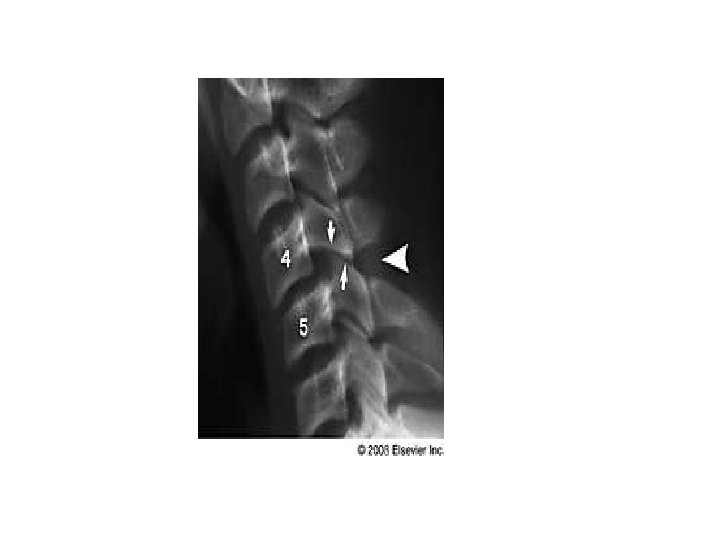

ANTERIOR SUBLUXATION • Disruption of the posterior ligament complex. Anterior subluxation of C 4 on C 5 is characterized by widening of the interspinous space (arrowhead), subluxation of the C 4 -C 5 interfacetal joints (arrows), and anterior rotation of the C 4 vertebra relative to C 5.

• • • Stable but potentially unstable during flexion Mechanism : hyperflexion Disruption of posterior ligament complex, anterior intact • • Stable – loss of normal cervical lordosis anterior displacement of body fanning of interspinous distance • • • Unstable – anterior subluxation >4 mm assoc. compression fracture >25% of affected body increase or decrease in normal disc space fanning of interspinous distance • •